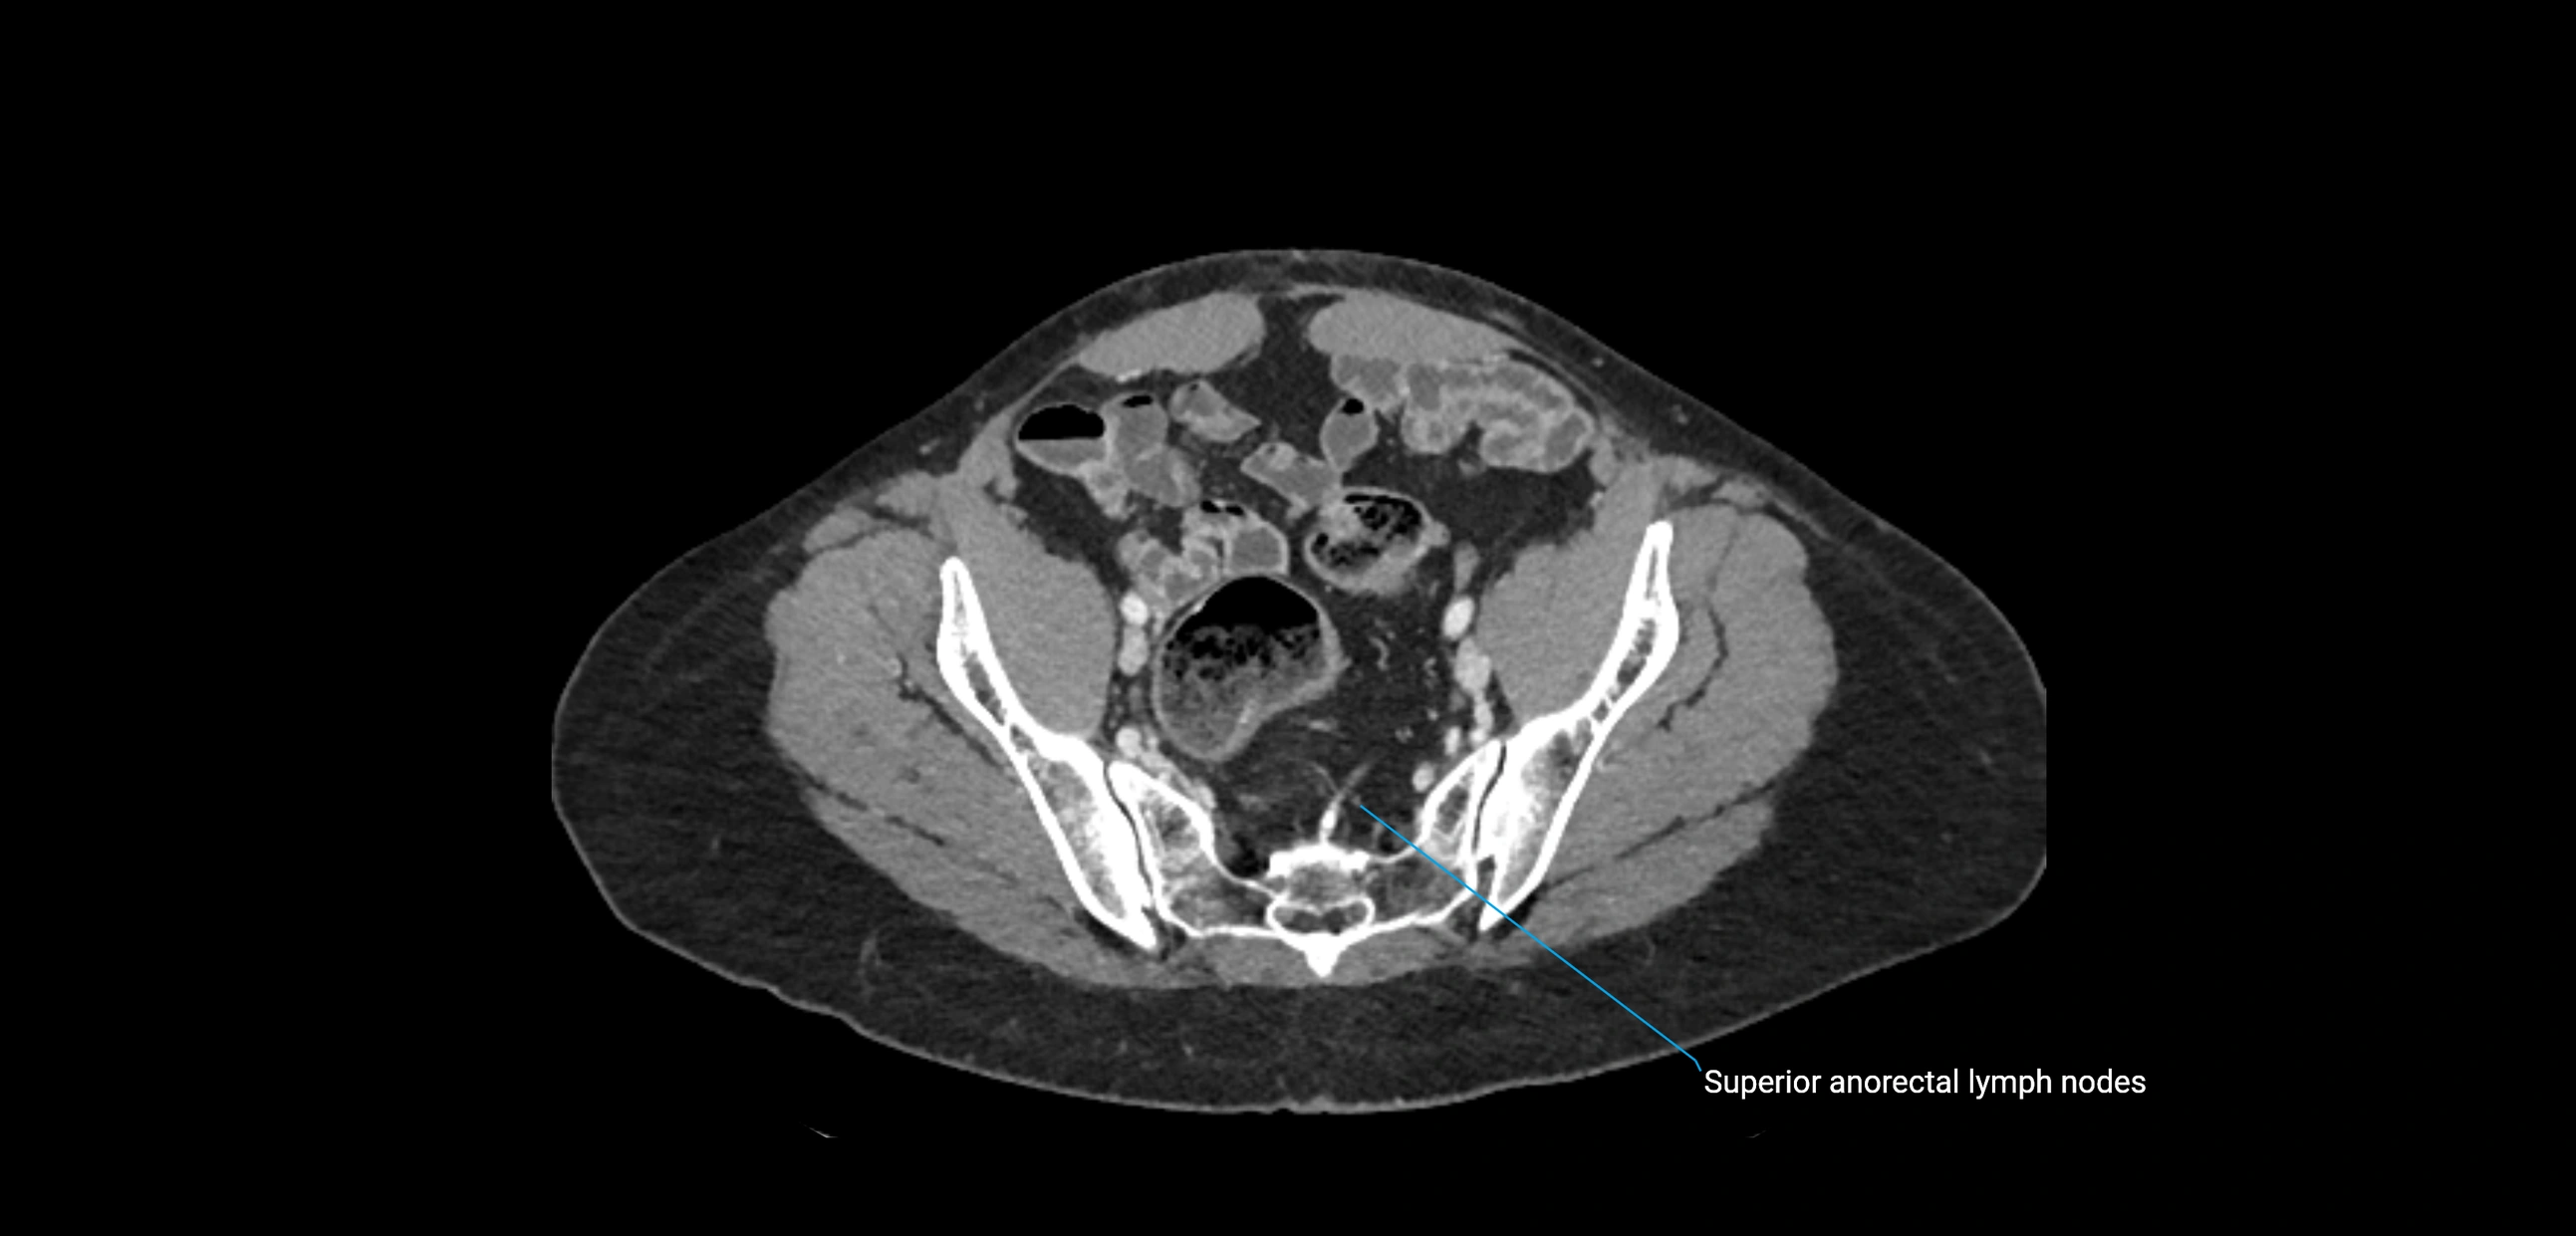

CT Appearance

CT Pre-Contrast:

• Nodes appear as soft-tissue density nodules adjacent to the aorta and IVC

• Calcification may be seen in chronic infections (e.g., tuberculosis)

CT Post-Contrast:

• Normal nodes enhance homogeneously

• Malignant nodes may show heterogeneous enhancement, central necrosis, or conglomerate formation

• Size >1 cm short axis is suspicious, though morphology and distribution are equally important

CT image

image